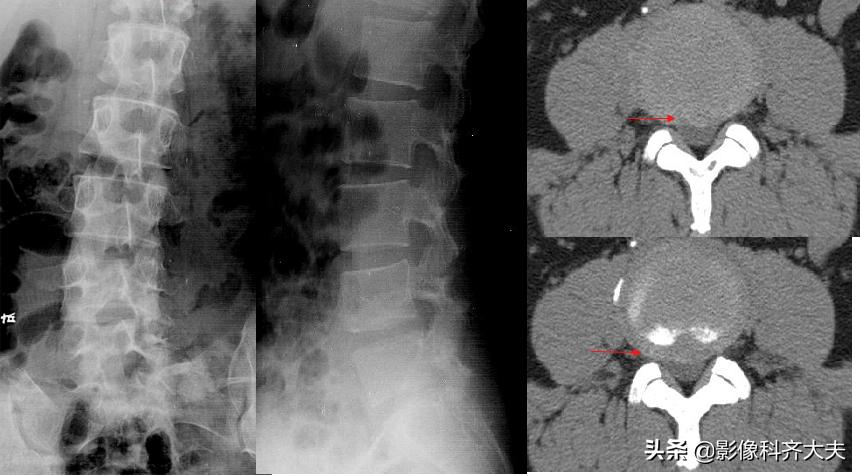

X 线 表 现

椎间隙均匀或不对称性狭窄(后宽前窄)

椎体边缘,尤其后缘出现骨赘

脊椎序列变直或侧弯

许莫氏结节:椎体上或下缘圆形或半圆形凹陷区,周围有硬化

间接征象:退行性变

正侧位示腰4、5间隙变窄,CT扫描示腰4、5间盘突出

CT:椎间盘突出(中央型)